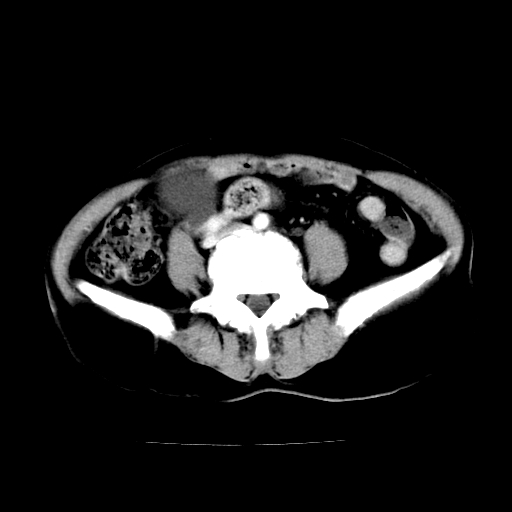

标题: CT24785:女,62岁,发现下腹部肿物半年。 [打印本页]

标题: CT24785:女,62岁,发现下腹部肿物半年。

女,62岁,发现下腹部肿物半年,下腹部不适。

老年女性患者,盆腔囊实性占位,ct增强不均匀强化,未见壁结节,未见腹水及盆腔积液,考虑附件囊腺瘤可能性大!